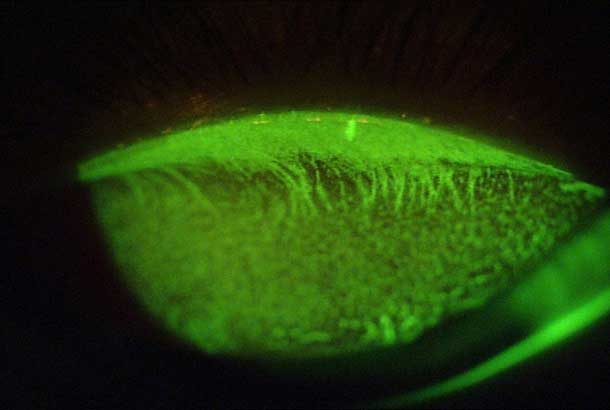

"category": "Cornea",

"detail": "<p>Endothelial edema</p>\n\n<h2>Symptoms</h2>\n\n<ul>\n\t<li>None</li>\n</ul>\n\n<h2>Signs</h2>\n\n<ul>\n\t<li>Black spots which appear to be &ldquo;holes&rdquo; on endothelium when viewed with specular reflection</li>\n\t<li>Intracellular edema of endothelial cells</li>\n\t<li>Maximum response occurs 10-20 minutes after lens insertion.</li>\n\t<li>Reduction in response occurs over initial weeks of lens wear.</li>\n</ul>\n\n<h2>Etiology</h2>\n\n<ul>\n\t<li>Local decrease in pH, associated with hypoxia and carbon dioxide build-up</li>\n\t<li>Typically occurs in unadapted wearers. Degree related to oxygen transmissibility of the lens material</li>\n</ul>\n\n<h2>Prevalence</h2>\n\n<ul>\n\t<li>Occasional</li>\n</ul>\n\n<h2>Differential Diagnosis</h2>\n\n<ul>\n\t<li><a href=\"/condition/62/\">Guttata</a></li>\n\t<li>See: <a href=\"/condition/62/\">Endothelial Changes &ndash; Differential Diagnosis</a></li>\n</ul>\n\n<h2>Management</h2>\n\n<ul>\n\t<li>No action required</li>\n\t<li>May consider refit into SiHy or high Dk GP lenses if response is severe</li>\n</ul>",